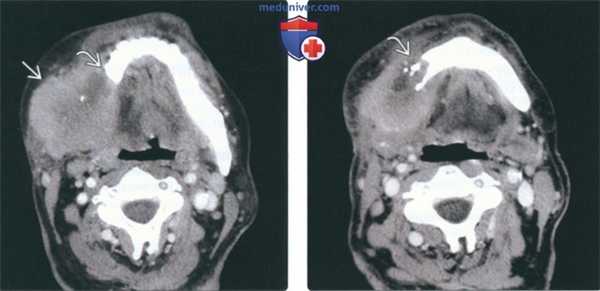

(Слева) На аксиальной МРТ (Т1 ВИ C+) в жевательном пространстве визуализируется лейомиосаркома высокой степени злокачественности, неравномерно накапливающая контраст и поражающая нижнюю челюсть. Большинство типов сарком жевательного пространства сложно дифференцировать в отсутствие костного или хондроидного матрикса.

(Справа) На корональной МРТ (Т1 ВИ С+ FS) у этого же пациента визуализируется контрастирующаяся опухоль с интракраниальным распространением через овальное отверстие а и поражением кавернозного синуса.

(Слева) На аксиальной МРТ (Т1ВИ) в жевательном пространстве визуализируется саркома Юинга в виде огромного объемного образования с гиперинтенсивным относительно мышц сигналом. Ветвь нижней челюсти разрушена, на этом изображении виден лишь ее мелкий фрагмент. Полоска окологлоточного жира смещена кнутри.

(Справа) На аксиальной МРТ (Т2ВИ FS) у этого же пациента определяется неоднородный сигнал крайне высокой интенсивности в опухоли. Хорошо различимый заглоточный лимфоузел слева является случайной находкой.